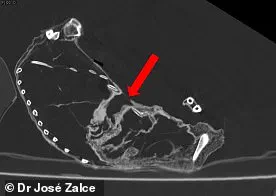

CT scans of Montserrat, who was between 16 and 25 years old, revealed a puncture wound to the chest, specifically between the fifth and sixth ribs.

CT scans of Montserrat (pictured) indicated she likely died from a puncture wound to the chest, specifically between the fifth and sixth ribs.

This injury, which appears to be the result of a sharp object, has been the subject of intense scrutiny.

Some researchers have theorized that the wound could have been inflicted by a projectile or a blade, while others suggest it may have been the result of a natural process, such as decomposition or postmortem damage.